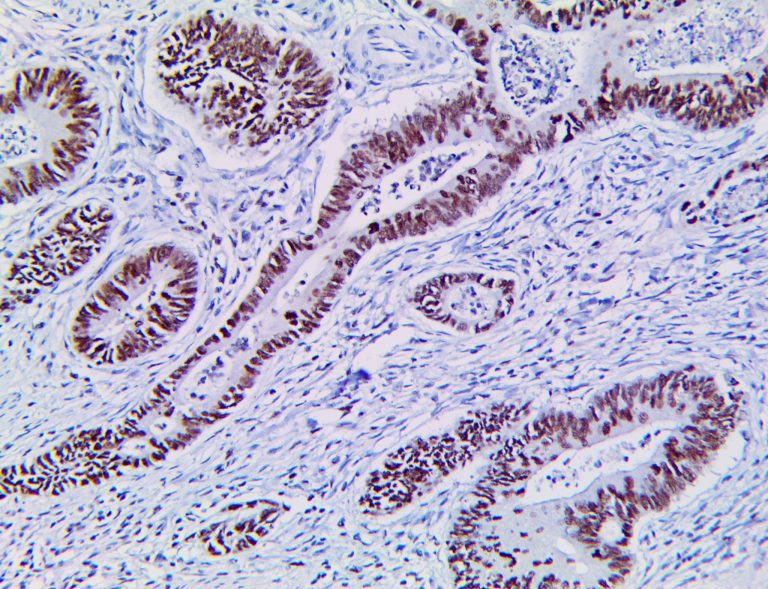

The first cytokines released are interleukin 1β (IL-1β) and tumor necrosis factor-α (TNF-α), which attract a variety of circulating white blood cells (WBCs) to the infection site, including neutrophils, monocytes, macrophages, and natural killer (NK) cells. This response, along with the antipathogenic chemicals released by these cells (i.e., complement), comprise the innate immune response. These cells directly attack the invading pathogen and also release additional cytokines, chief among them interleukin-1 and 6 (IL-6). IL-6 is essential for invoking the adaptive immune response, which calls T-cells, B-cells, and T helper (Th) cells to the infection site. IL-6 also stimulates further recruitment, proliferation and activation of macrophages.

It is the ICU physician who is most likely to witness one of the deadliest manifestations of the abnormal immunological response, the cytokine storm syndrome (CSS). This response is also referred to by some as the cytokine release syndrome (CRS). CSS is characterized by continuous activation and expansion of macrophage and lymphocyte populations, which secrete large amounts of cytokines, causing the cytokine storm. This massive cytokine release is akin to hemophagocytic lymphohistiocytosis (HLH) disease, a syndrome characterized by initial unchecked and persistent activation of cytotoxic T lymphocytes and NK cells.

This activation induces inflammatory monocytes to highly express IL-6, starting a localized and then systemic cascade effect that results in hyperproduction of IL-6, which accelerates the inflammatory process. Because IL-6 also increases vascular permeability, excessive levels cause blood vessels to become very leaky. This, along with clotting factors released from vascular endothelial cells, stimulates the coagulation cascade, resulting in microthrombosis (tiny clots), which leads to ischemia and tissue death of the kidney, intestines, heart, liver, brain and extremities.